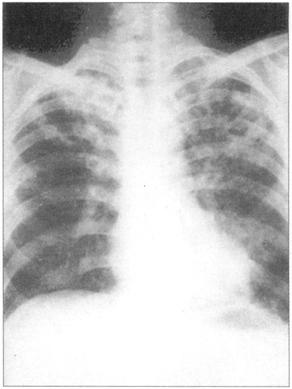

①周围性发绀及周围静脉扩张是由COPD引起的CO2潴留的主要特征(图76)。②脊柱侧后凸常预示患者有某种呼吸系统疾病的倾向(图77)。③结核的X线表现(图78)。④肺尖部结核所致的纤维化多引起上胸部变平(图79),由于脊柱常受累,故多有成角。⑤支气管肺癌(图80)。⑥大叶肺炎患者常伴发单纯疱疹病毒感染(图81、图82)。⑦如肺组织萎陷(如气胸),则胸片上无法看到肺纹理(图83)。

图81 大叶性肺炎,这个患者有右肺实变

图82 单纯疱疹病毒感染在大叶性肺炎患者常见